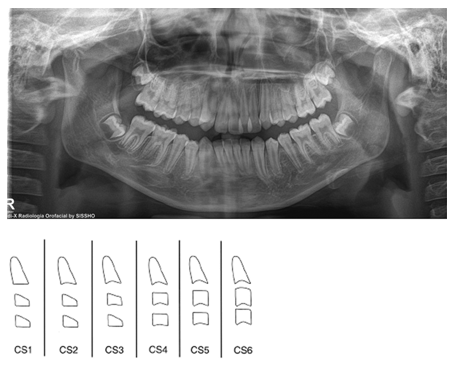

Male patient 11 years old with permanent dentition, skeletal class II, straight profile, compressed airway, cervical bone maturation stage CS2, presents compression of the upper arch and deep palate, mandibular retrogantism, with an upper model discrepancy -7.5mm, Bolton analysis shows anterior discrepancy of 5.4mm, the Pont analysis shows a transverse length deficit of -9.20mm, severe crowding in the upper jaw, moderate crowding in the lower jaw, facial biotype is mild Dolicofacial, in the periodontal examination aberrant lingual and labial frenulum was observed; the lower one limits the lingual movement. The indicated examinations included: intraoral photography, panoramic and lateral skull radiographs. When evaluating the results it was corroborated the existence of a transverse micrognathism of the maxilla (Figure 1).

Figure 1.

Comments

With disjunction, orthopedic expansion is performed to separate the midpalatal suture by applying forces between 3 and 10 ounces against the lateral sectors of the upper jaw. For each millimeter of posterior expansion, 0.7 mm of arch length is obtained.7 The importance of these disjunctors lies in the fact that they make it possible to correct, without surgical intervention, the contractions of the transverse diameter of the upper arch, which are related to a skeletal base defect. These can often be found associated with class I, II or III malocclusions. The use of the Hyrax expander appliance has the advantage of being more hygienic and comfortable than those with extensions or acrylic plates, besides the fact that results can be seen within days. The effectiveness of this screw in rapid maxillary expansion was demonstrated, as it contributed to improve facial esthetics and the patient's smile. Rapid maxillary expansion performed with a Hyrax type disjunctor in a patient in stage CS2 has a high probability of success. Undoubtedly, a spontaneous repositioning of the mandible to a more anterior position was obtained and changes were observed in the nostrils which were compressed and are now permeable, contributing to better breathing and cerebral oxygenation in the patient (Figure 6 & 7).